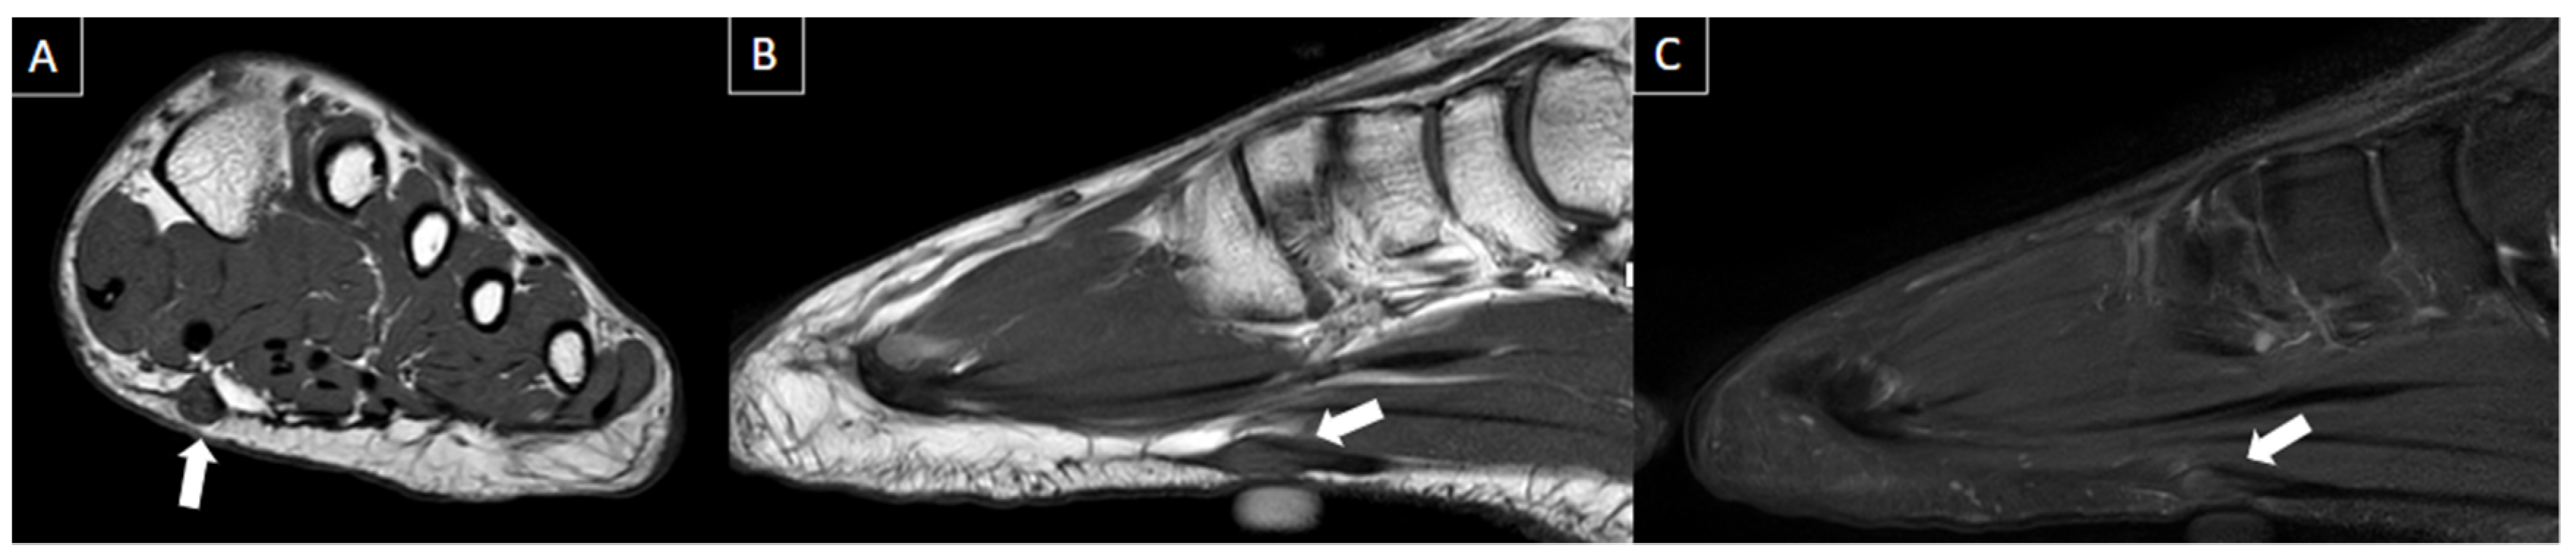

6.5. Plantar Fibromatosis

| Plantar fibromatosis | Pain due to mass effect or infiltration of adjacent muscles or neurovascular structures. | Fusiform-shaped nodule at the plantar fascia away from the calcaneal insertion, either hypoechoic or isoechoic to the fascia. | Isointense plantar fascia nodule on T1-weighted and T2-weighted fat-suppressed images with contrast enhancement. |